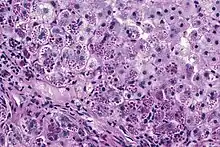

Photomicrograph of a liver biopsy from a patient with alpha-1 antitrypsin deficiency. The PAS with diastase stain shows the diastase-resistant pink globules that are characteristic of this disease.

With A1AT deficiency, the pathogenesis of the lung disease is different from that of the liver disease, which is caused by the accumulation of abnormal A1AT proteins in the liver, resulting in liver damage.[9] As such, lung disease and liver disease of A1AT deficiency appear unrelated, and the presence of one does not appear to predict the presence of the other.[9] Between 10 and 15% of people with the PiZZ genotype will develop liver fibrosis or liver cirrhosis, because the A1AT is not secreted properly and therefore accumulates in the liver.[18] The mutant Z form of A1AT protein undergoes inefficient protein folding (a physical process where a protein chain achieves its final conformation). 85 percent of the mutant Z form are unable to be secreted and remain in the hepatocyte.[9] Nearly all liver disease caused by A1AT is due to the PiZZ genotype, although other genotypes involving different combinations of mutated alleles (compound heterozygotes) may also result in liver disease.[9] A liver biopsy in such cases will reveal PAS-positive, diastase-resistant inclusions within hepatocytes.[9] Unlike glycogen and other mucins which are diastase sensitive (i.e., diastase treatment disables PAS staining), A1AT deficient hepatocytes will stain with PAS even after diastase treatment - a state thus referred to as "diastase resistant". The accumulation of these inclusions or globules is the main cause of liver injury in A1AT deficiency. However, not all individuals with PiZZ genotype develop liver disease (incomplete penetrance), despite the presence of accumulated mutated protein in the liver.[9] Therefore, additional factors (environmental, genetic, etc.) likely influence whether liver disease develops.[9]